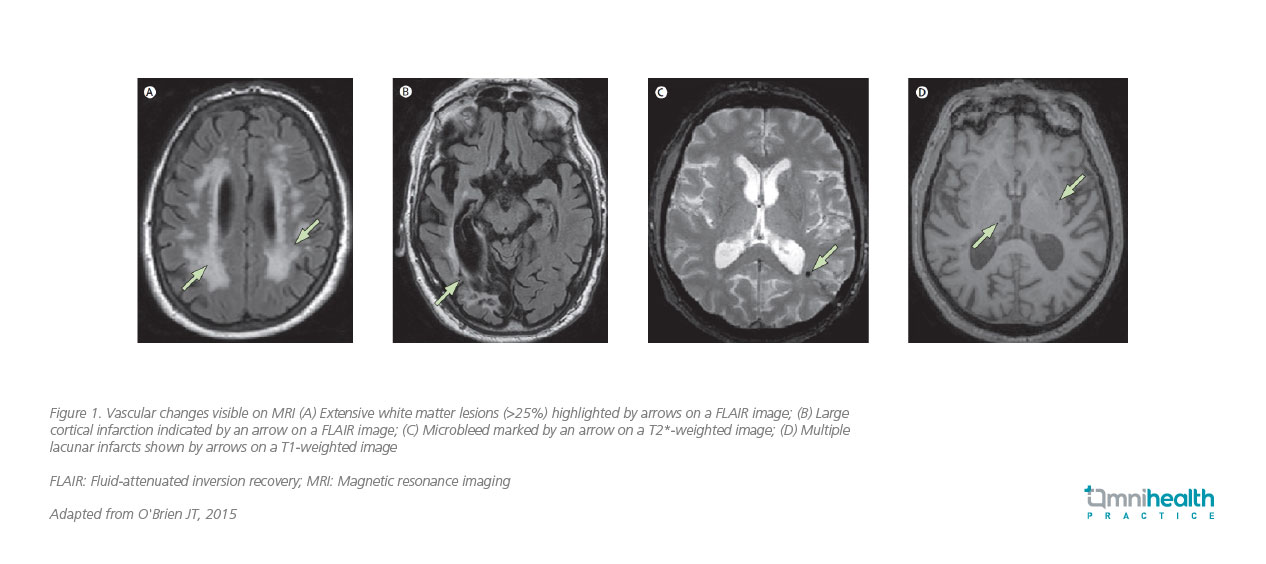

Hence, diagnosing VaD requires a multifaceted approach.2 Clinicians typically begin with a thorough history and physical examination, looking for signs of stroke or other neurological deficits.6 Neuropsychological assessments, such as the Mini-Mental State Examination (MMSE) or Montreal Cognitive Assessment (MoCA), are used to evaluate cognitive function.6 Neuroimaging remains central to diagnostic workup.7 The United Kingdom (UK) National Institute for Health and Care Excellence (NICE) recommends structural brain imaging in all cases of suspected dementia, with magnetic resonance imaging (MRI) preferred when a vascular etiology is suspected.7 MRI can detect features suggestive of VCI, including strategic infarcts, lacunes, white matter hyperintensities, cerebral microbleeds, enlarged perivascular spaces (PVS), and brain atrophy (figure 1).7 It can visualize recent small infarcts for several weeks after onset, supporting identification of temporal associations between vascular injury and cognitive decline.7